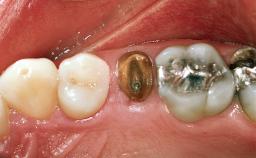

Replacement of the Four Maxillary Incisors with a Fixed Dental Prosthesis Using an Immediate Loading Protocol

In November 2001, a 53-year-old female presented seeking advice and options for treatment of her maxillary incisor teeth. She was dissatisfied with both the functional and esthetic qualities of her existing restorations. Her medical health was excellent, and she reported no contraindications to dental care. On presentation, the patient’s dental health was less than ideal. Although she had no probing depths greater than 3 mm, she suffered from generalized chronic adult periodontitis and displayed multiple sites of bleeding on probing. Her remaining dentition was heavily restored, and many teeth had been endodontically treated. Areas of recurrent dental caries were noted on many teeth. Radiographically and clinically, the maxillary incisor teeth exhibited large areas of active caries, and after the splinted crowns had been removed, the teeth were determined to be non-restorable.

Prosthesis Type FDP

Mesio-Distal Space Adequate for the replacement of all missing teeth